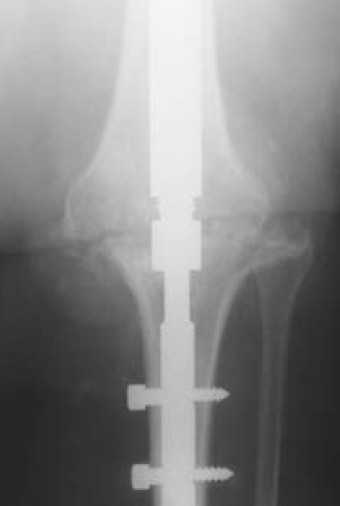

B. Modular nail

Modular nail

Concept

- single knee incision

- tibial and femoral components inserted through knee & then joined together

- different sizes for femur and tibia